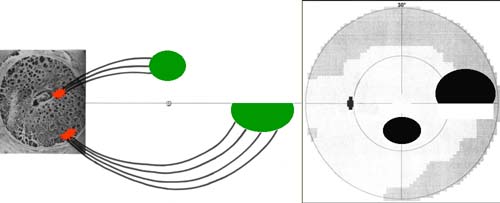

Buňky v centrální části sítnice se začínají diferencovat nejdříve a již za týden jejich výběžky dosahují až k terči. Tak vzniká základ makulopapilárního svazku. Během dalších několika dnů se diferencují gangliové buňky v perifernějších oblastech sítnice. Těm, které rostou z temporální strany, překáží v cestě ke zrakovému nervu již vytvořený makulopapilární svazek a musí jej obloukovitě obejít. Vlákna rostoucí z gangliových buněk z nasální strany takovou překážku na cestě nemají a jejich průběh ke zrakovému je přímý. Tímto způsobem během několika dní vzniká vrstva nervových vláken. Její uspořádání nám umožňuje pochopit lokalizaci skotomů zorného pole.

Výpadky nervových vláken na sítnici a graficky na perimetru podle Minclera

Korelace lokálního výpadku nervových vláken se změnami zorného pole dle Minclera

Když exkavace zasahuje až okraji terče dochází k poškození vláken, která vedou až do temporální části sítnice k tělům gangliových buněk, uloženým v sousedství horizontálního švu. Poškození těchto buněk a jejich axonů se projeví nasálním skokem s arkuátním Bjerumovým skotomem.

Pokud exkavace nedosahuje k samému okraji terče (miskovité exkavace), svědčí to pro poškození vláken z povrchnější vrstvy, které směřují k gangliovým buňkám uloženým paracentrálně – periferně od makulopapilárního svazečku. Poškození těchto buněk a jejich axonů se projeví paracentrálními skotomy.